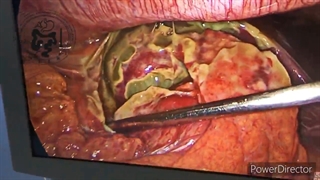

جراحی لاپاروسکوپی ترمیم فتق کشاله ران سمت راست، یک روش کم تهاجمی برای اصلاح فتق در ناحیه کشاله ران است که از طریق چند برش کوچک در شکم انجام می‌شود. در این روش، جراح از یک دوربین کوچک به نام لاپاراسکوپ و ابزارهای جراحی مخصوص برای ترمیم ناحیه ضعیف شده در دیواره شکم که باعث ایجاد فتق شده است، استفاده می‌کند. مزایای این روش شامل برش‌های کوچکتر، درد کمتر بعد از عمل، بهبودی سریع‌تر و بازگشت سریع‌تر به فعالیت‌های روزمره نسبت به جراحی باز سنتی است.در حین عمل لاپاراسکوپی ترمیم فتق کشاله ران، بیمار معمولاً تحت بیهوشی عمومی قرار می‌گیرد. جراح پس از ایجاد برش‌های کوچک، لاپاراسکوپ را وارد شکم کرده و با استفاده از تصاویر بزرگنمایی شده که روی مانیتور نمایش داده می‌شوند، ساختارهای داخلی را به دقت بررسی می‌کند. سپس، فتق به جای خود بازگردانده شده و ناحیه ضعیف شده در دیواره شکم با یک مش (patch) مخصوص تقویت می‌شود. این مش از مواد سازگار با بدن ساخته شده و به مرور زمان با بافت‌های اطراف ادغام می‌شود تا از عود مجدد فتق جلوگیری کند. تثبیت مش می‌تواند با استفاده از بخیه، چسب جراحی یا منگنه‌های مخصوص انجام شود که انتخاب روش بستگی به نظر جراح و شرایط خاص بیمار دارد. بعد از اتمام ترمیم، ابزارها خارج شده و برش‌ها با بخیه‌های کوچک بسته می‌شوند. دوره نقاهت بعد از جراحی لاپاراسکوپی معمولاً کوتاه‌تر از جراحی باز است و بیماران معمولاً می‌توانند پس از چند روز به فعالیت‌های سبک خود بازگردند، اما رعایت دستورالعمل‌های پزشک و اجتناب از فعالیت‌های سنگین در دوره بهبودی بسیار مهم است.